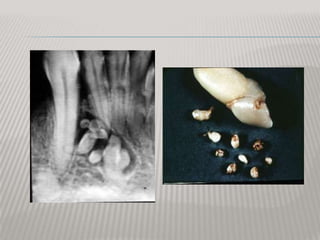

COMPOUND ODONTOMA

It is a collection of small radiopaque masses,

some or all may be tooth-like structures

“denticles”.

It tends to occur in 62% in the anterior region of

the maxilla and usually associated with the crown

of an unerupted canine. It is formed by exuberant

growth of the dental lamina or into a number of

small enamel organs by proliferation of the

enamel organ.

COMPOUND ODONTOMA It isa collection of small radiopaque masses, some or all may be tooth-like structures “denticles”. It tends to occur in 62% in the anterior region of the maxilla and usually associated with the crown of an unerupted canine. It is formed by exuberant growth of the dental lamina or into a number of small enamel organs by proliferation of the enamel organ.